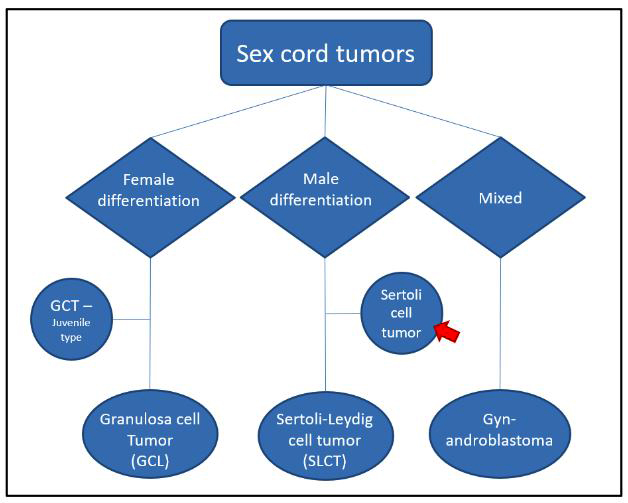

Definition / general | Essential features | ICD coding | Epidemiology | Sites | Pathophysiology | Etiology | Diagrams / tables | Clinical features | Diagnosis | Laboratory | Radiology description | Prognostic factors | Case reports | Treatment | Gross description | Gross images | Frozen section description | Microscopic (histologic) description | Microscopic (histologic) images | Positive stains | Negative stains | Molecular / cytogenetics description | Sample pathology report | Differential diagnosis | Additional references | Practice question #1 | Practice answer #1Cite this page: Welter SM, Khalifa MA. Sertoli cell tumor. PathologyOutlines.com website. https://www.pathologyoutlines.com/topic/ovarytumorsertoli.html. Accessed September 18th, 2025.

- Pure sex cord neoplasm of the ovary composed of Sertoli cells most commonly arranged in a tubular pattern

- Rare to no Leydig cells present

Essential features

- Solid or hollow tubules with or without other histologic patterns containing cuboidal cells that are positive for sex cord markers

- Sertoli-Leydig cell tumor:

- Abundant Leydig cell component (MelanA positive)

- Pure sex cord tumor

C. Pure sex cord tumor. Sertoli cell tumor is a pure sex cord neoplasm of the ovary composed of Sertoli cells most commonly arranged in a tubular pattern. Sertoli cells are positive for inhibin and SF1. Answer D is incorrect because no Leydig cells, which are positive for MelanA and are stromal in nature, are present. Answer B is incorrect because the tumor is negative for neuroendocrine markers. Answer A is incorrect because the tumor is negative for EMA and PAX8.